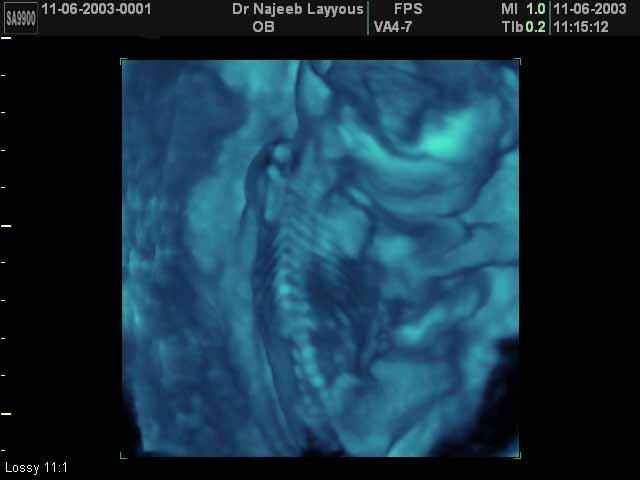

- Fetal Skeleton Ultrasound Photos